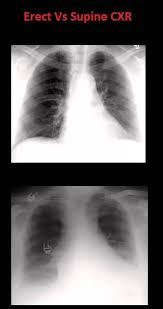

How To Interpret A Chest X Ray Lesson 3 Assessing Technical Quality X Ray Animal Adaptations Physical Education Games

Basics Of Reading Chest Xray Complete Guide To Cxr Beginners Medicforyou In 2020 Radiology Imaging X Ray Radiology Technologist